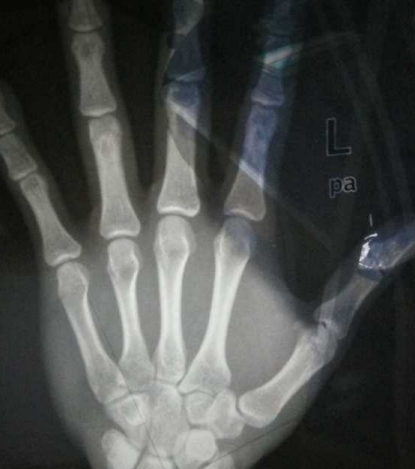

骨齡偏大或偏小都會影響孩子的身高,預防孩子生長過早或過快的問題,觀察骨齡進展的快慢,找出影響孩子長個的因素及時的調整,那么怎么預防骨齡提前?下面八寶網小編帶來介紹。

例如男孩12周歲,骨齡在11-13周歲區間是正常,骨齡大于或小于實際周歲2年以上,就要警惕內分泌疾病或早發育。

特別注意:一般孩子在14、15歲時骨骺就接近閉合,生長基本停止。家長不能盲目等待孩子“晚長”,最終會耽誤孩子成年身高。

按骨齡發育速度可以分為三種情況:

骨齡正常,也就是骨齡與年齡相差在-1到 1歲之間;

骨齡偏大,也就是骨齡與年齡相差≥1歲,意味著孩子有可能性早熟;

骨齡落后,骨齡與年齡相差≤1歲,意味著有可能生長激素缺乏。

但要注意的是通常情況下孩子的骨齡和年齡一般都是相符的,上下浮動不超過 1 歲,而在疾病狀態下,骨齡與實際年齡往往不一致。

如果發現孩子的骨齡與實際年齡不符,一定要盡早找出原因。比如說進展迅速的早發育或者青春期快速進展的孩子,他們的骨齡常常比實際年齡大。

骨骺是骨骼發育的關鍵部位,由于性激素有明顯的促進骨骺閉合的作用,孩子就會表現為骨齡偏大,假如沒有及時治療,等到骨骺完全閉合了,孩子的生長潛能也就消失了,以后的身高發育肯定會受影響。骨齡落后的孩子常常因為缺乏生長激素、軟骨發育不全等等疾病而導致身高增長緩慢,雖然理論上說由于骨齡較小,實際生長空間應該大于相應年齡者,但由于存在生長異常,每年的實際生長幅度會小于正常兒童,后期生長空間也有限,而家長還在等待孩子“晚長”,最終會耽誤孩子成年身高。